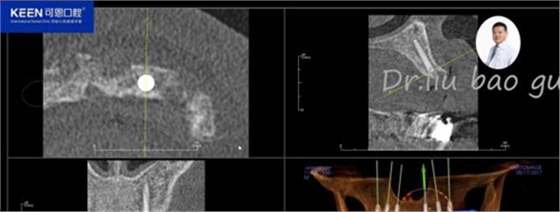

手術(shù)前種植軟件設(shè)計(jì)方案

數(shù)字化種植導(dǎo)板設(shè)計(jì)及制作